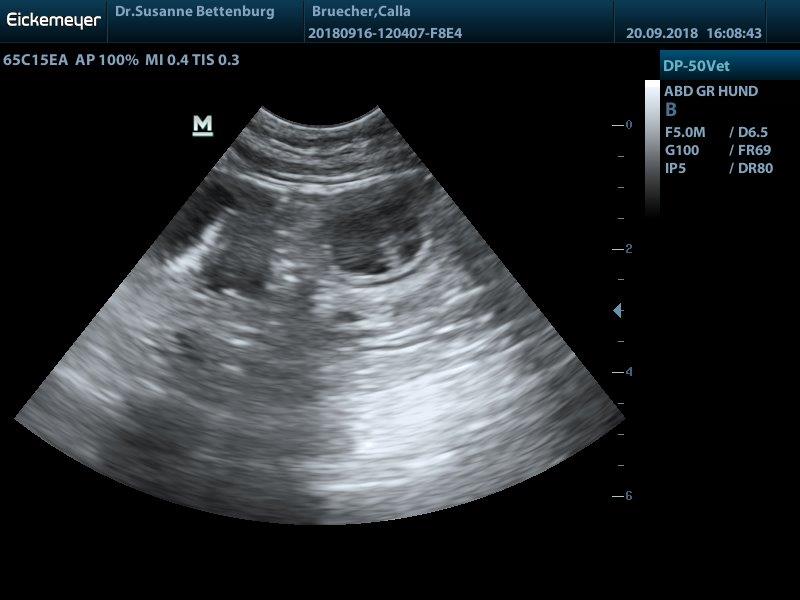

Juhuuu Calla ist trächtig...

wir haben viele kleine Baby's gesehen und erwarten ende Oktober einen normal großen Wurf